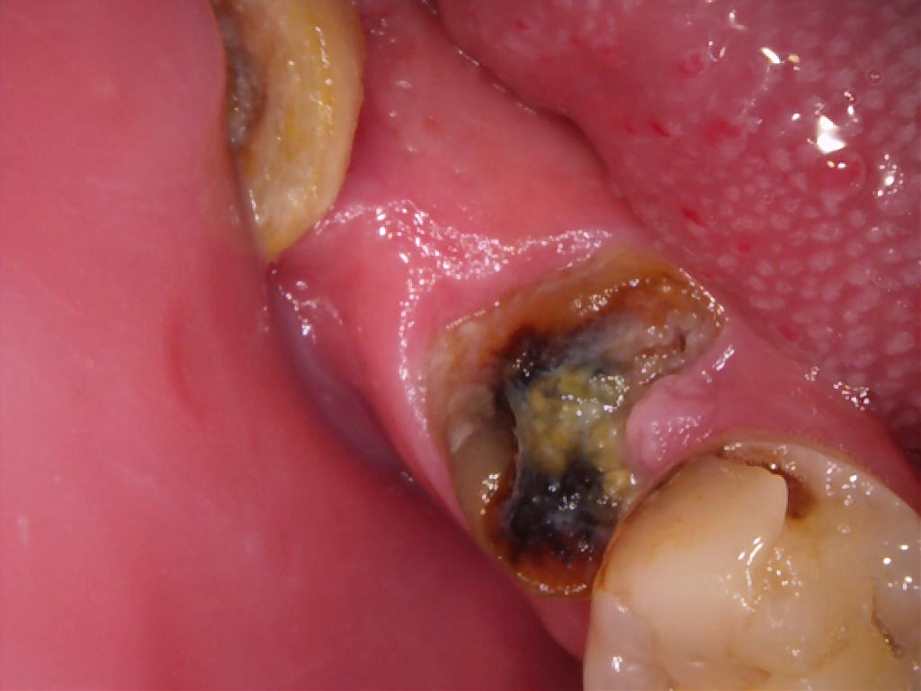

治療前

-

- 治療名称

- 右下6番残根抜歯後のインプラント治療

- 患者の症状

- 残根抜歯後インプラントを入れたい。

- 治療内容

- まず、CT撮影による精密な骨の分析・治療計画を立てガイドを使いインプラント埋入しインプラントが骨と結合するのを待つ間に仮の歯を入れます。その後本歯を作成して装着しました。

- 治療期間・回数

- インプラント埋入からジルコニアセットまで六か月

- 費用

※自由診療となります - ■総額¥330,000(税込み) ■内訳:埋入(ガイド込み)¥200,000、仮歯¥20,000、被せ物(ジルコニア)¥80,000